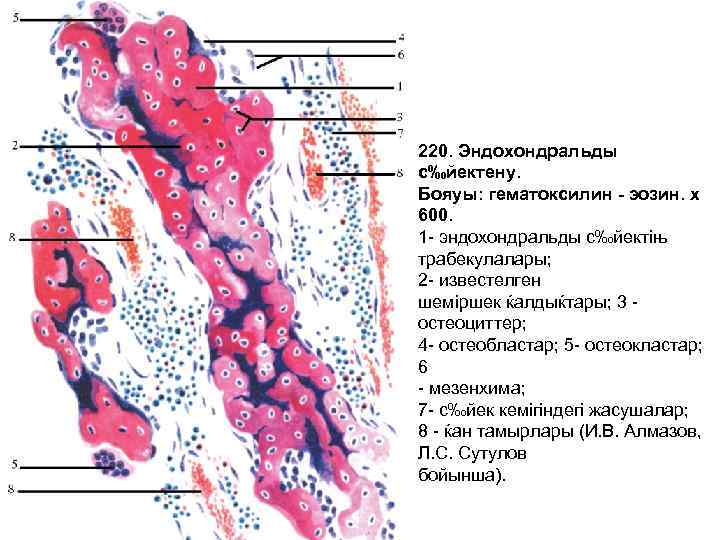

220. Эндохондральды с‰йектену. Бояуы: гематоксилин - эозин. х 600. 1 - эндохондральды с‰йектіњ трабекулалары; 2 - известелген шеміршек ќалдыќтары; 3 остеоциттер; 4 - остеобластар; 5 - остеокластар; 6 - мезенхима; 7 - с‰йек кемігіндегі жасушалар; 8 - ќан тамырлары (И. В. Алмазов, Л. С. Сутулов бойынша).